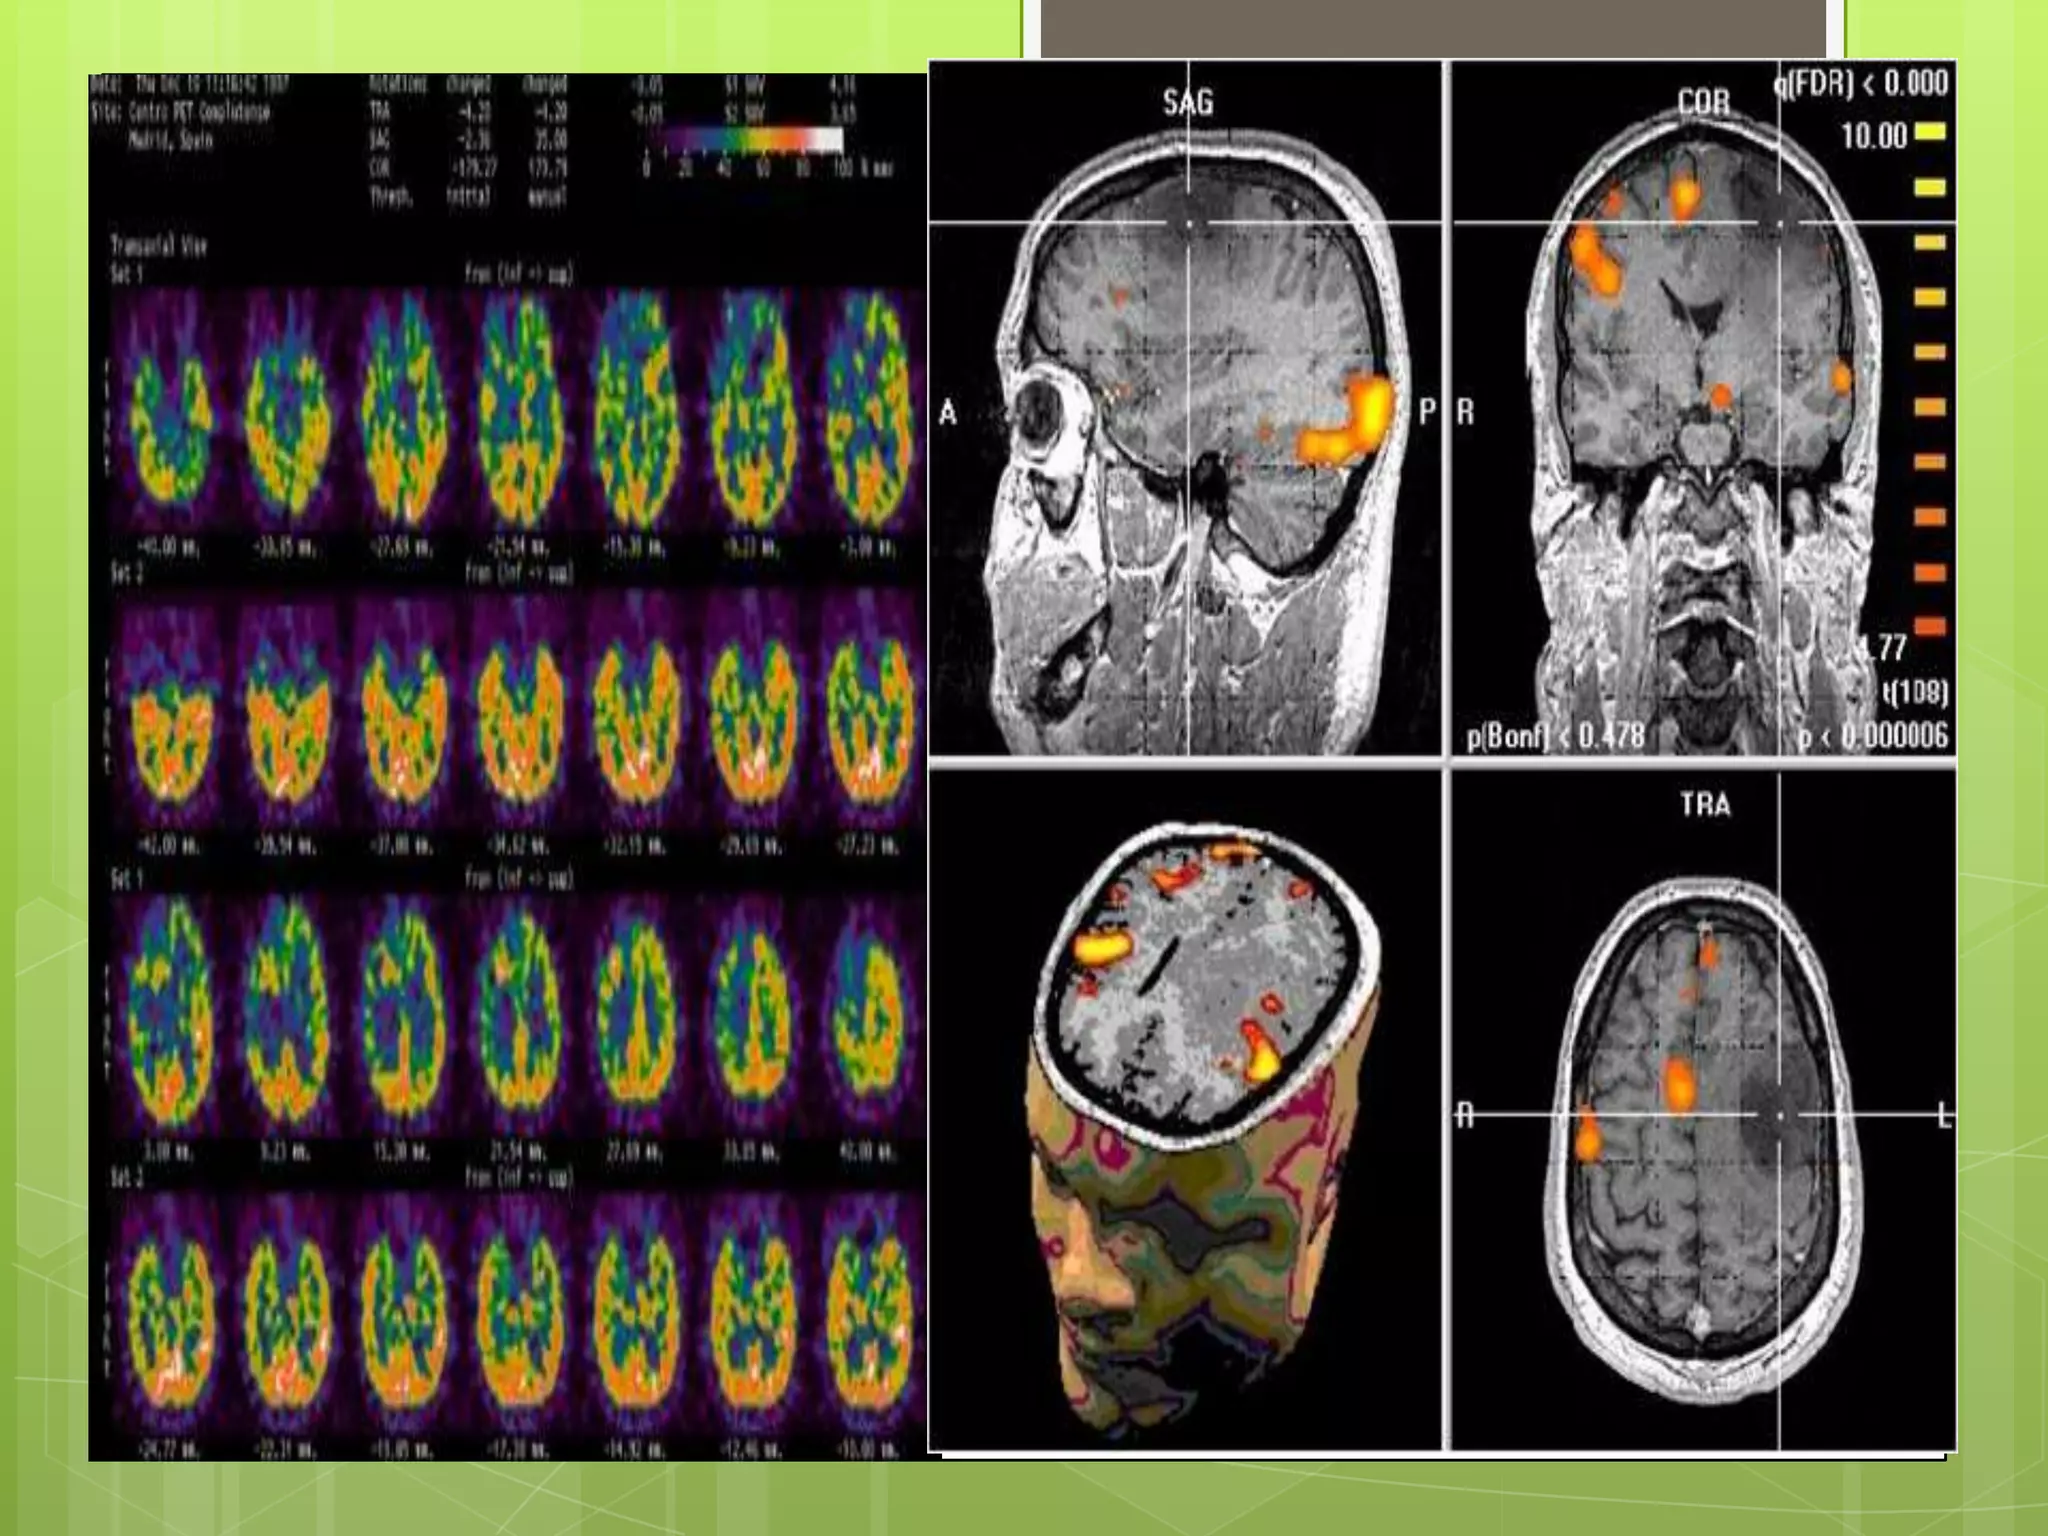

LA TOMOGRAFIA CON

EMISION DE POSITRONES

 Proporciona imagines bi y tridimensionales de la

actividad cerebral midiendo los isótopos

radioactivos que se inyectan dentro del torrente

sanguíneo.

 Las tomografías PET cerebrales se usan para

detectar o resaltar tumores y tejidos enfermos, medir

el metabolismo celular y tisular, mostrar el flujo

sanguíneo, evaluar a los pacientes con trastornos

convulsivos que no responden a la terapia médica y

pacientes con ciertos trastornos de la memoria, y

determinar cambios cerebrales luego de lesiones o

abuso de drogas, entre otros.

LA TOMOGRAFIA CON EMISIONDE POSITRONES  Proporciona imagines bi y tridimensionales de la actividad cerebral midiendo los isótopos radioactivos que se inyectan dentro del torrente sanguíneo.  Las tomografías PET cerebrales se usan para detectar o resaltar tumores y tejidos enfermos, medir el metabolismo celular y tisular, mostrar el flujo sanguíneo, evaluar a los pacientes con trastornos convulsivos que no responden a la terapia médica y pacientes con ciertos trastornos de la memoria, y determinar cambios cerebrales luego de lesiones o abuso de drogas, entre otros.